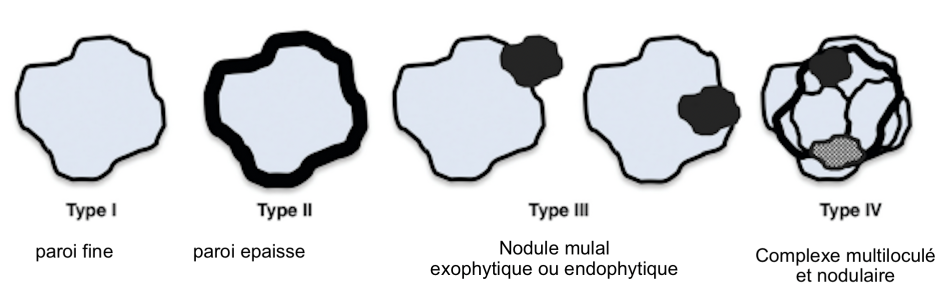

kyste cyst lung tumor tumeur adénocarcinome cancer lésion kystique cystic enlargement suspect classe classification

kyste cyst lung tumor tumeur adénocarcinome cancer lésion kystique cystic enlargement suspect classe classification